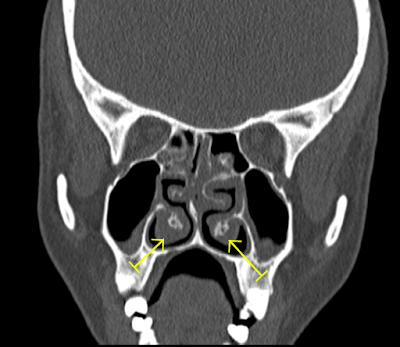

Hypertrophied nasal turbinates l Bilateral maxillary l ethmoidal and sphenoidal sinusitis

Bilateral maxillary sinusitis coronal view

• Mucosal thickenings are noted in both maxillary  antrum, ethmoidal air cella and sphenoidal sinus

• Nasal turbinates are seen hypertrophied.

• Osteomeatal complex is blocked on left side.